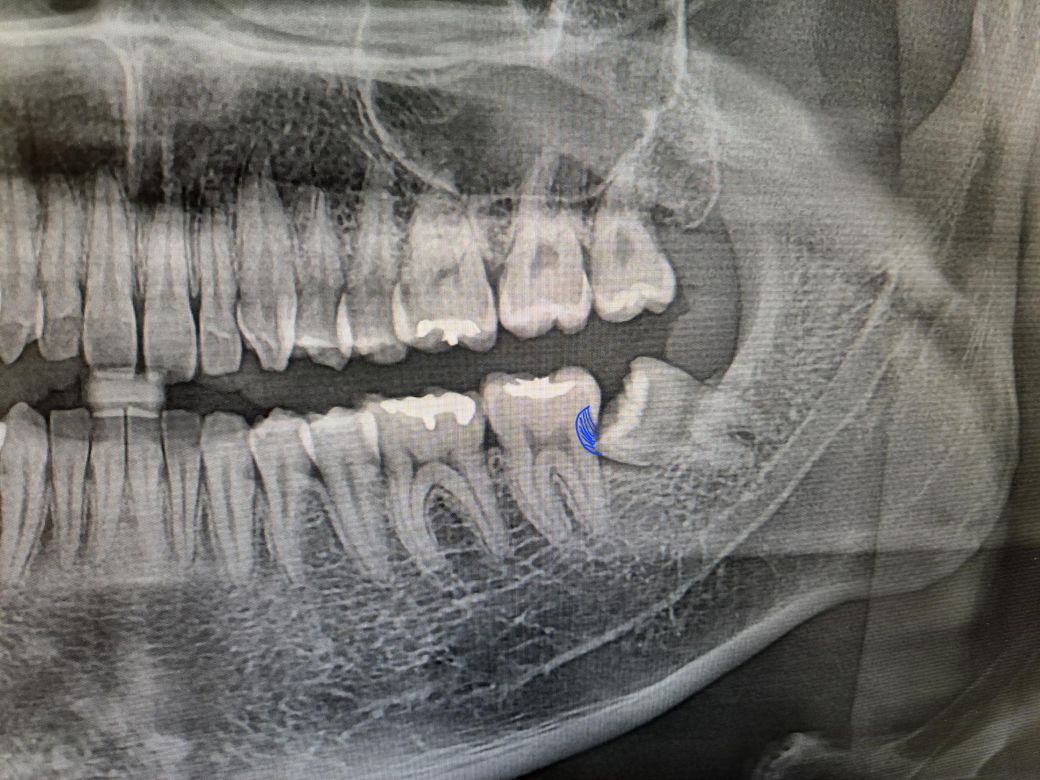

사랑니 옆의 어금니가 저렇게 충치가 생긴 상태인데요

• 1번 째 사진

빼봐야 압니다 파노라마 사진보고 사랑니 옆 어금니가 썩었다고 단언하는 건 엉터리입니다 물론 확률상 충치가 있는 경우가 많지만 사랑니 빼고 다시 정밀한 치근단 사진(작은 엑스레이 사진) 찍어보면 충치 아니고 그냥 왜곡(엑스레이상 그림자의 일종)인 경우도 간혹 있습니다

저게 옆면 충치가 맞다면, 크라운을 씌워야 하므로 신경치료는 피하긴 어렵습니다

해당 사진만으로는 정확한 여부 알 수는 없으나 사진상 보이는 것 보다는 실제 더 깊을 가능성이 높습니다. 깊다면 단순 우식 제거뿐만 아니라 신경치료 병행할 가능성 옾으며 정확한 판단은 사랑니 발치 후 확인해봐야할 것으로 보입니다. 너무 미루지 마시고 지치 발치하시길 바랍니다.